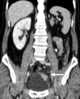

Congenital absence or aplasia of kidney